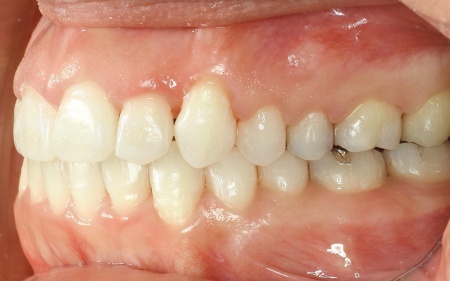

拝見したところ、奥歯で噛んだ際に上下の前歯が触れ合わず、隙間ができている状態でした。

これは開咬(かいこう)と呼ばれ、前歯で食べ物を噛み切るのが難しい噛み合わせです。

加えて全体的に歯が重なり合ってデコボコに生えており、歯磨きがしにくく、審美性にも悪影響がでています。

また、骨格的には下顎が後下方に位置しており、お顔全体が縦に長いタイプでした。